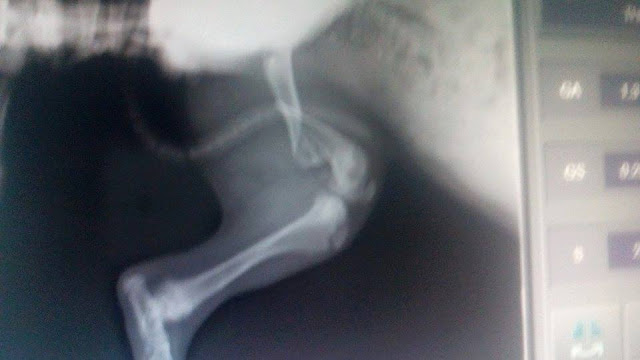

1 καταγμα η Κλειω και 3 ο Buter στα ποδια

Η Κλειω έχει συντριπτικό κάταγμα μηριαιου με παρεκτοπηση.

Θα πρεπει να γίνει χειρουργική αναταξη με πλάκα.

Ο Butter έχει συντριπτικό κάταγμα μηριαιου με παρεκτοπηση και αμφοτεροπλευρο κάταγμα κνημης περονης. Ιδια διαδικασία αναταξης.

Ειναι στην ουσια 4 χειρουργεια και το κόστος είναι 800 ευρώ.